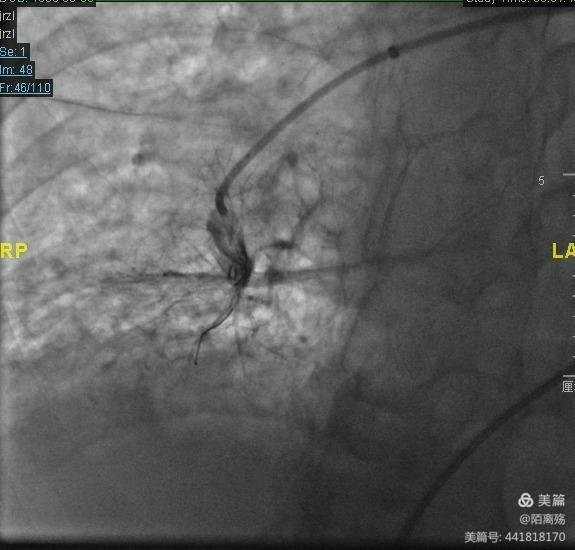

术者徐鸥主任、汤银江主任行肺动脉球囊扩张成形术(BPA)

机化血栓狭窄病变血管部位行肺动脉造影示图。